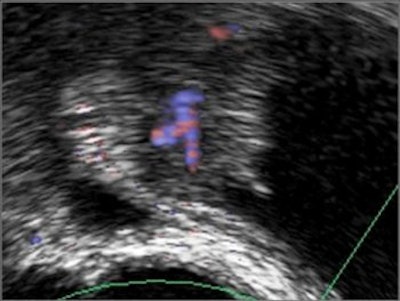

Freehand scanning was used for 3D data acquisition, and surface rendering and multiplanar reconstruction for 3D data analysis. Power Doppler ultrasound was used to differentiate the extent of infiltration. The criteria for staging were based on the vascularity of the tumor's basement. The gold standard was the histomorphology results.

| Power Doppler ultrasound criteria for staging vascularity of the tumor basement. Above, submucosal vessels; second, half muscle wall vascular. Below, whole muscle wall vascular; second image, few vessels in the perivesical walls; third image, massive flow in the perivesical fat. Images courtesy of Dr. Veronika Gazhonova, Russian President Medical Center and Russian State Medical University. |